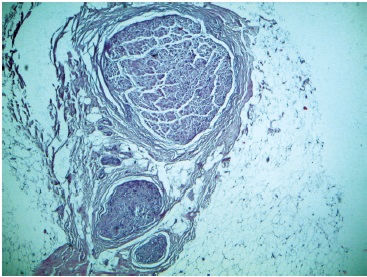

Перед окончанием исследования, после осуществления ротации комплекса трансплантатов, моторные ветви ГМБН к мышцам передней группы голени маркировали, после чего забирали их фрагменты для гистологического исследования с целью определения диаметра этих ветвей на их поперечном срезе (рис. 3).

Рис. 3. Микрофотография глубокого малоберцового нерва и его ветвей. Окраска гематоксилином и эозином. Ув. ×40 / Fig. 3. Micrograph of the deep peroneal nerve and its branches. Staining with hematoxylin and eosin. Mag. ×40

В 6,3% наблюдений (4 конечности) были обнаружены две ветви, иннервирующие длинный разгибатель большого пальца стопы на 94,3 и 119,9 мм ниже головки малоберцовой кости. Диаметры нервных ветвей, измеренные при гистологическом исследовании с помощью микроскопа, представлены в таблице 3. Результаты измерения диаметров нервных структур показали, что выделение нервов таких диаметров невозможно без увеличения. Попытки проведения этого этапа без использования бинокулярной лупы приводили к повреждению как минимум двух моторных ветвей ГМБН.